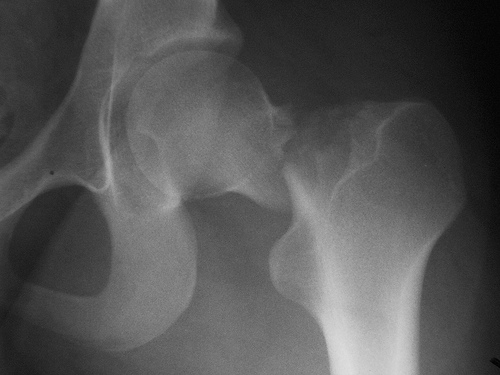

Cirugía de cadera ultrarrápida

En pacientes con fractura de cadera, la cirugía en las primeras seis horas del diagnóstico no obtuvo mejores resultados que la realizada a las 24 hs del mismo. The Lancet, 29 de febrero de 2020.